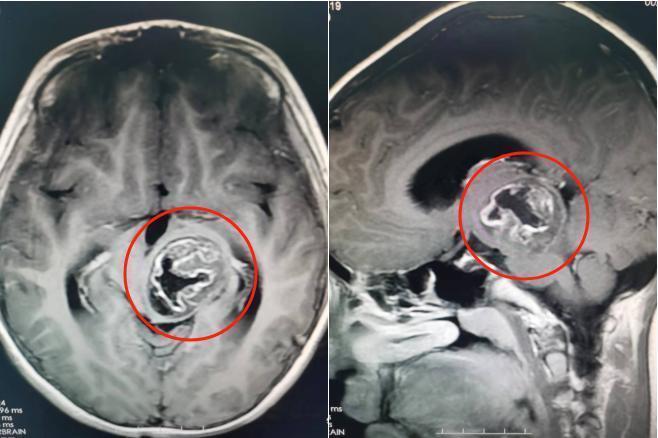

脑部检查结果提示,轩仔的左侧丘脑、中脑存在占位性病变,大小约为39mm×30mm×35mm。该院副院长鲁明在接诊时,发现患儿左眼斜视明显、右上肢肌力下降,推断是脑肿瘤引起的症状。

术前影像资料